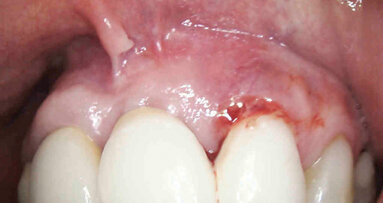

La paziente è stata sottoposta a profilassi antibiotica tramite somministrazione di 2 g di amoxicillina/acido clavulanico (Augmentin, GlaxoSmithKline) un’ora prima della chirurgia. La paziente inoltre ha eseguito sciacqui orali con clorexidina 0,2% (Corsodyl, GlaxoSmithKline) per due minuti e assunto 100 mg di nimesulide (Aulin, Roche). Il trattamento post-operatorio è proseguito con l’assunzione di 1 g di amoxicillina/acido clavulanico ogni 12 ore per 6 giorni e nimesulide 100 mg ogni 12 ore per 3 giorni, oltre alla continuazione degli sciacqui orali con clorexidina 0,2% per 10 giorni. L’anestesia locale è stata eseguita mediante infiltrazione di articaina all’1% ed epinefrina 1:100.000 (Molteni Dental). Dopo aver aperto due lembi gengivali tra le posizioni 21–23 e 11–13, gli impianti sono stati posizionati attraverso l’impiego della dima chirurgica. Gli impianti sono stati inseriti ottimizzandone l’ingombro vestibolo-palatale, in relazione al ridotto spessore crestale (Fig. 4). L’intervento si è concluso eseguendo una sutura a punti semplici staccati con utilizzo di filo riassorbibile Vycril Rapid 5-0 (Johnson & Johnson).

Acquisita l’impronta digitale postoperatoria, questa è stata inviata allo stesso laboratorio specializzato (IDI Makers) per la fabbricazione delle protesi provvisorie. Il decorso post-operatorio è stato privo di eventi significativi. Al termine dell’intervento, non sono state applicate viti di guarigione. Ciò ha favorito il trofismo dei tessuti e ha permesso di ottenere un’ottimale coesistenza senza interferenze degli impianti con i provvisori applicati all’apparecchio ortodontico. La sutura è stata rimossa a 10 giorni dall’intervento. La paziente è stata poi sottoposta a controlli postoperatori di rito fino ad arrivare al momento della finalizzazione protesica. È stata quindi sottoposta a profilassi antibiotica27, 28 e anestesia per effettuare delle modeste incisioni che non interessassero il connettivo profondo al fine del posizionamento delle protesi provvisorie. Queste sono state montate su IDI Base B1ONE con ingaggio senza spalla e con allestimento di un ideale profilo di emergenza finalizzato a un’ottimale guarigione dei tessuti molli perimplantari.

Fig. 4_Procedimento chirurgico finalizzato all’inserimento degli impianti B1ONE HIGH in posizione 22 (2,7 x 12 mm) e 12 (3,2 x 12 mm) mediante chirurgia guidata. Al termine dell’inserimento, è visibile la connessione intracoronale dell’impianto monopezzo.